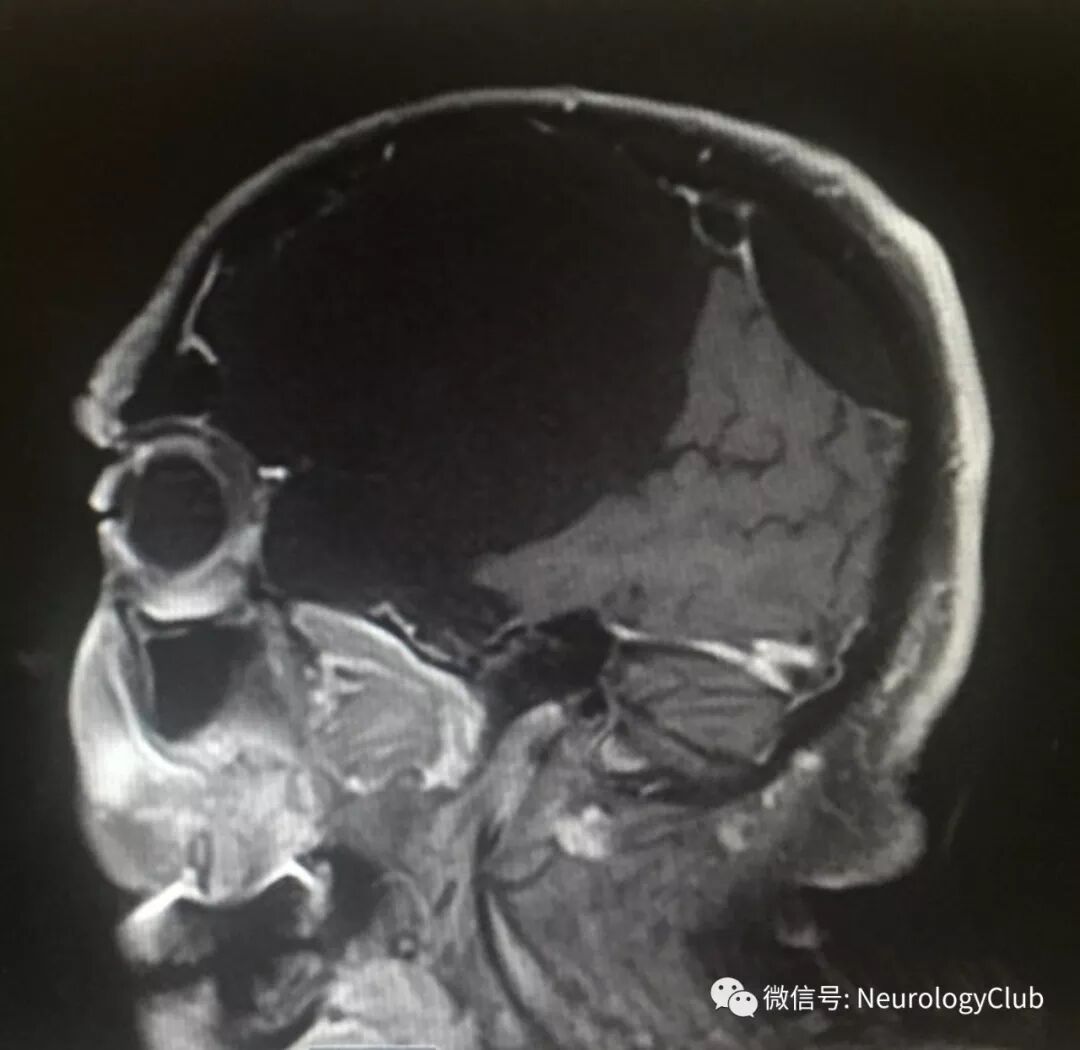

头颅MRI如下:

(图3:矢状位T1WI可见囊性病灶伴明显占位效应)